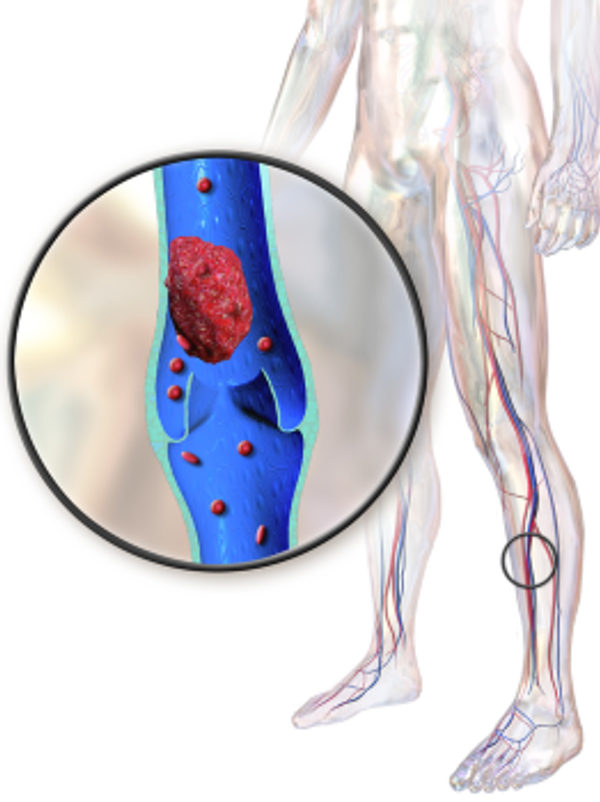

Manchmal kommt es zu einer Blutgerinnung, obwohl kein Grund dafür besteht; es gibt keine Wunde zu heilen. Dann bildet sich irgendwo im Körper ein Gerinnsel in einem Blutgefäß, das den Blutfluss in diesem Gefäß ganz oder teilweise blockiert. Theoretisch kann sich ein solches Gerinnsel überall im Körper bilden. Dementsprechend hat ein Gerinnsel auch unterschiedliche Folgen.

Ein Gerinnsel in einer Arterie (arterielle Thrombose) kann unter anderem zu einem Herzinfarkt, einem Schlaganfall oder einer Blockade der Beine führen. Befindet sich ein Gerinnsel in einer Vene (venöse Thrombose), kann es in oberflächlichen oder tieferen Venen auftreten. Eine oberflächliche Venenthrombose tritt häufig bei Krampfadern auf, eine tiefe Venenthrombose in den tieferen Gefäßen, meist im Bein.

Je nachdem, in welchem Blutgefäß sich die Thrombose befindet, sind die Symptome, wie bereits erwähnt, unterschiedlich. Bei einer tiefen Venenthrombose im Bein kann es zu einem Spannungsgefühl kommen und das Bein oder der Fuß können sich sehr schwer anfühlen. Das Bein kann auch anschwellen und sich warm anfühlen als an anderen Stellen. Normalerweise wird die Haut rot oder bläulich und glänzt.